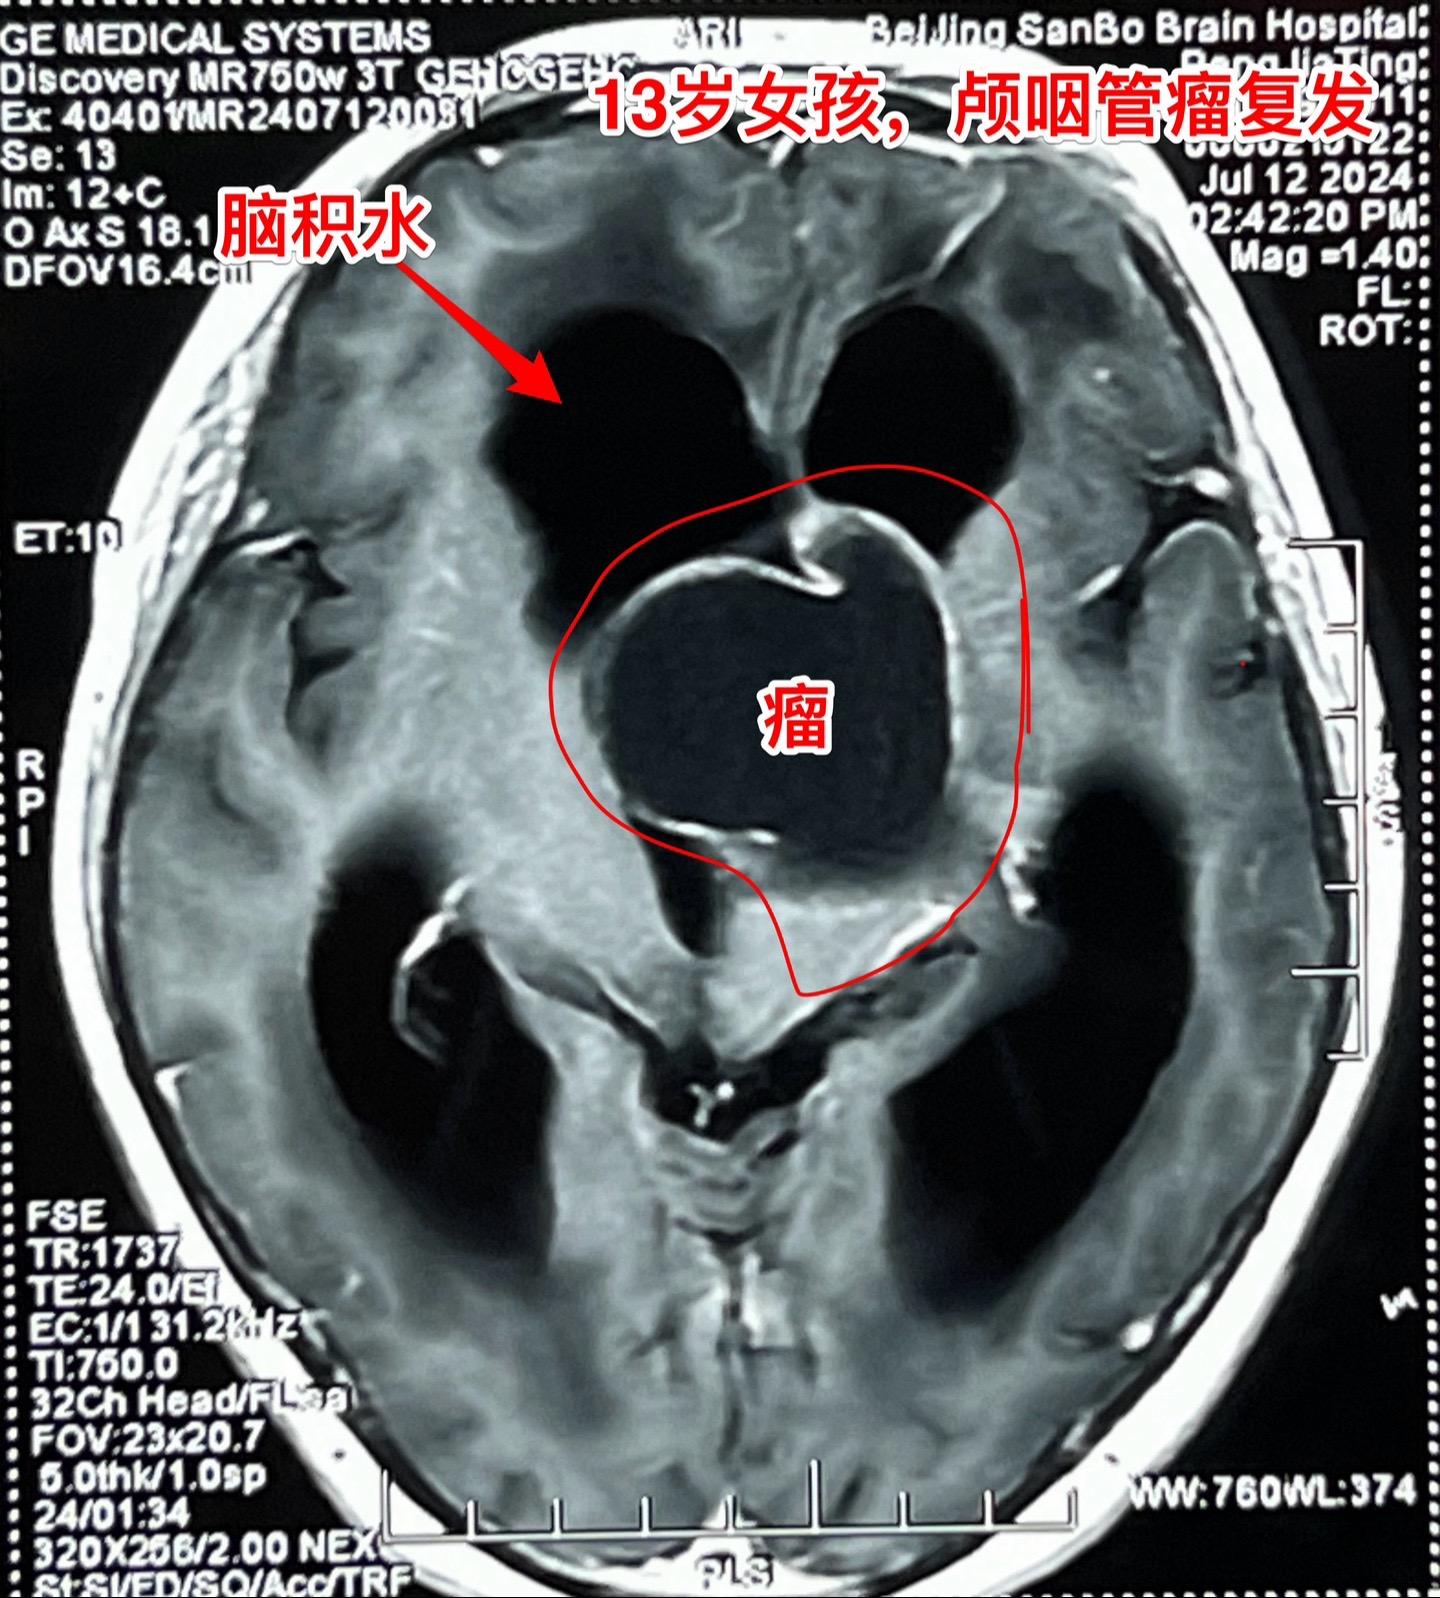

复发的巨大颅咽管瘤,难度很大。13岁四川女孩子,2022年6月在外院行开颅手术切除颅咽管瘤。半年后颅咽管瘤复发,家长采用中药治疗。中药控制颅咽管瘤的效果也不理想,肿瘤还在继续生长。 复发肿瘤体积越来越大,患儿曾经出现过头痛、呕吐、多睡症状。经过补充糖皮质激素后症状有好转。额部骨头逐渐出现隆起,见图4、5。 2024年7月16日作了开颅手术,将颅咽管瘤完全切除。肿瘤体积大,压迫脑干,而且与周围的血管粘连紧密,手术过程很艰难,最终获得完全切除。 手术后患儿很虚弱